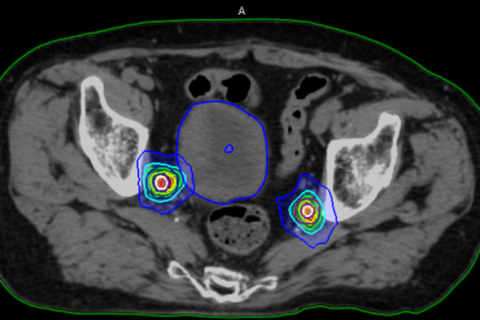

少数個転移(オリゴ転移)に対する定位放射線治療(ピンポイント照射)について

がんが他の部位に転移している場合でも、転移の数が限られている状態を「少数個転移(オリゴ転移)」と呼びます。 このような状態では、転移した病変一つひとつを狙って治療することで、病状の進行を抑えることが期待できる場合があります。

少数個転移に対する治療法の一つが、定位放射線治療(ピンポイント照射)です。

定位放射線治療は、病変の位置を正確に捉え、周囲の正常な組織への影響をできるだけ抑えながら、狙った部位に集中的に放射線を照射する高精度な治療法です。

骨やリンパ節などに少数の転移がみられることがあり、こうした病変に対して定位照射を行うことで、薬物療法(ホルモン療法や化学療法)と組み合わせた治療の選択肢が広がる場合があります。

当院では、少数個転移に対する定位放射線治療を、4回から20回に分けて行っています。

転移の部位や、周囲に副作用が起こりやすい臓器が近い場合には、照射回数を増やして1回あたりの放射線量を抑え、安全性を高める工夫を行っています。

前立腺がんの骨盤内リンパ節転移(複数個)に対する定位照射